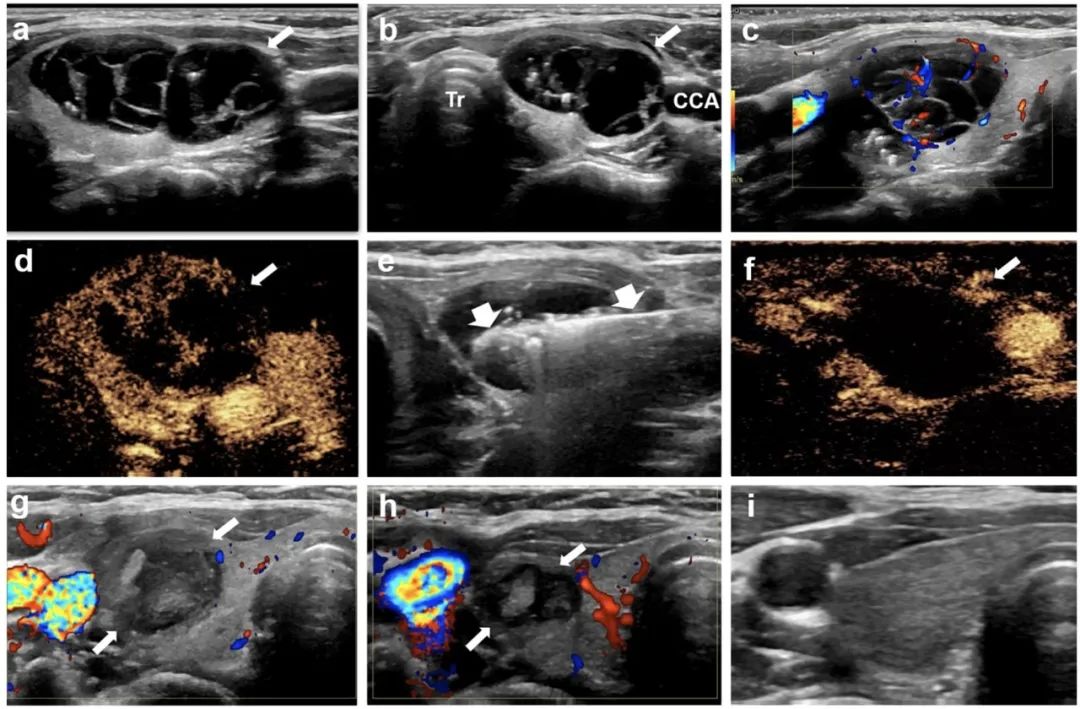

針對該問題,石文媛主任團隊開創(chuàng)性地將微波消融技術應用于兒童良性甲狀腺結節(jié)的治療。連續(xù)分析了2018年1月至2021年12月在北京兒童醫(yī)院接受經皮微波消融治療的有癥狀良性甲狀腺結節(jié)患兒25名,共 34枚結節(jié)。所有患兒均隨訪半年以上(中位隨訪時間12個月,范圍6 - 48個月)。結果顯示:經皮微波消融治療后,結節(jié)體積逐漸減?。ㄎ⒉ㄏ谇爸形惑w積5.86 mL,末次隨訪評估中位體積0.34 mL),末次隨訪評估體積縮小率達到85.03%,技術有效率達91.2%。結節(jié)相關壓迫癥狀、美容相關問題均得到顯著改善。術后一個月隨訪甲狀腺功能維持在正常范圍之內,提示微波消融在滅活甲狀腺結節(jié)的同時不影響正常甲狀腺功能。

甲狀腺右葉囊性為主結節(jié),微波消融后3年,病灶完全消失